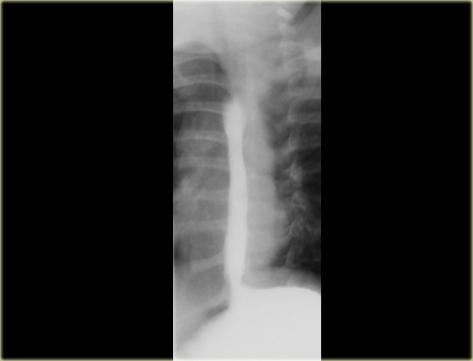

Thực quản mèo: A, B: Cho thấy các nếp ngang mảnh của thực quản; C: Hình ảnh chụp muộn hơn trong quá trình thăm khám không còn thấy các nếp này

Thực quản mèo

Cần phân biệt các nếp đồng tâm mảnh, xuất hiện thoáng qua của thực quản mèo với các nếp dày hơn, gián đoạn, cố định gợi ý sẹo xơ hóa theo chiều dọc do viêm thực quản trào ngược.

Đặc điểm của thực quản mèo bao gồm:

- Các vân ngang do co thắt cơ niêm mạc

- Bình thường ở loài mèo

- Thường thoáng qua và không có ý nghĩa bệnh lý

- Có thể liên quan đến trào ngược dạ dày thực quản hoặc viêm thực quản